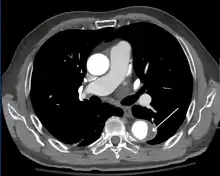

Computed tomography

Computed tomography angiography is a fast, non-invasive test that gives an accurate three-dimensional view of the aorta. These images are produced by taking rapid, thin-cut slices of the chest and abdomen, and combining them in the computer to create cross-sectional slices. To delineate the aorta to the accuracy necessary to make the proper diagnosis, an iodinated contrast material is injected into a peripheral vein. Contrast is injected and the scan performed using a bolus tracking method. This type of scan is timed to injection to capture the contrast as it enters the aorta. The scan then follows the contrast as it flows through the vessel. It has a sensitivity of 96 to 100% and a specificity of 96 to 100%. Disadvantages include the need for iodinated contrast material and the inability to diagnose the site of the intimal tear.

CT with contrast demonstrating aneurysmal dilation and a dissection of the ascending aorta (type A Stanford)- Chest CT with descending (type B Stanford) aortic dissection (red circle)

Type A dissection with pericardial effusion as a result.